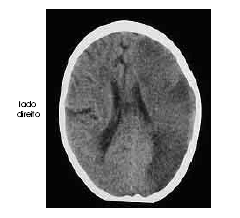

Um homem com 67 anos de idade, lavrador, deu entrada no pronto-socorro após ter sido encontrado, em sua casa, no chão e com dificuldade para falar e deambular. O paciente morava sozinho e os parentes não sabiam informar sobre uso de medicações ou patologias pregressas. Na avaliação, o neurologista identificou afasia mista, hemianopsia homônima direita e hemiparesia direita de predomínio braquifacial. Apesar de apresentar sonolência, o paciente ficava alerta ao chamado. A pressão arterial era de 180 mmHg × 90 mmHg. Foram solicitados exames complementares e de imagem, dos quais uma das imagens é reproduzida abaixo.

De acordo com o caso clínico acima, julgue os subseqüentes.